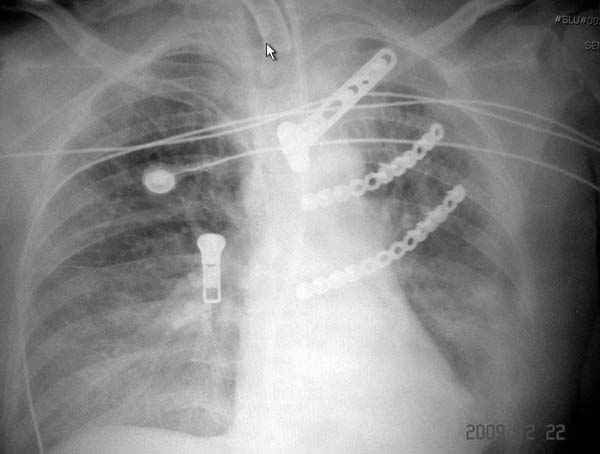

На седьмые сутки нами совместно с торакальным хирургом сделана операция по фиксации грудинно-ключичного сочленения и переломов ребер.

После кожного разреза обнаружили полный разрыв грудной мышцы и повреждение перикард от уровня второго до восьмого ребер. Хирург находился с нами и после нашей работы зафиксировал повреждение перикарда и разрыв грудной мышцы.

Пластина из Synthes http://int.synthesmatrixrib.com/html/Overview.5.0.html